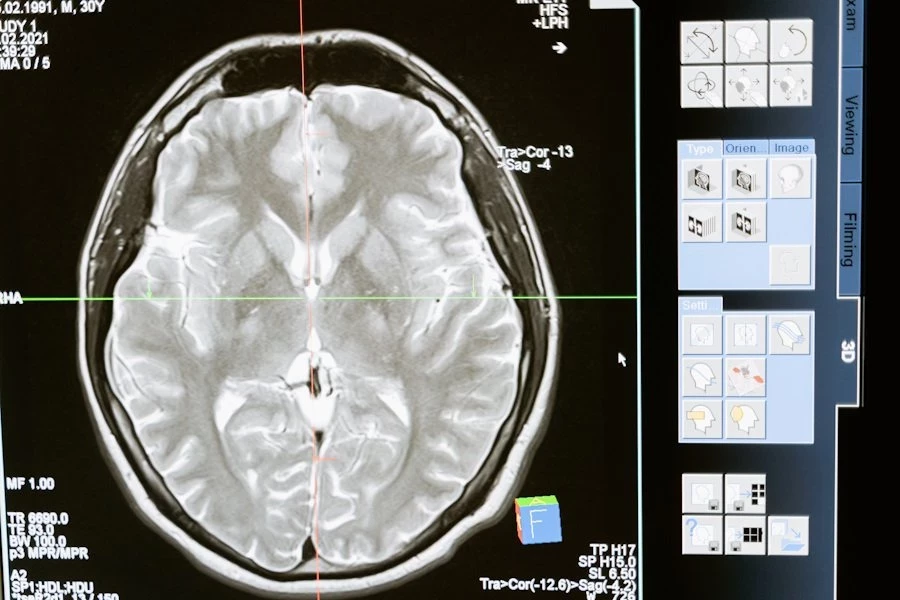

Согласно публикации на Science Advances, синаптическая пластичность, способность мозга изменять свою структуру в ответ на опыт и обучение, считается ключевым фактором формирования памяти. Однако, до недавнего времени не было четкого понимания о том, каким образом полимеризация актина, ответственная за стабильность дендритных шипиков — важных структурных элементов нейронов, связанных с образованием синапсов, влияет на кодирование памяти.

Исследователи использовали специально созданную форму протеинкиназы LIMK1, которая направленно воздействует на ADF/кофилин, ключевой модификатор актина. После активации этой формы LIMK1 в организме мышей, было отмечено долговременное увеличение дендритных шипиков и усиление синаптической передачи в гиппокампе, области мозга, играющей важную роль в формировании памяти.